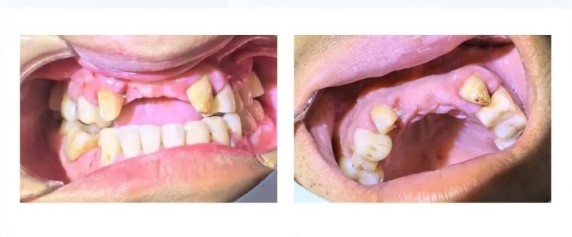

Examination findings: A4 porcelain crown repair, loose. A3 is loose, A2-B2 missing, B3 tooth preparation. Gingival swelling.

Oral cavity photograph

Frontal Occlusion Image